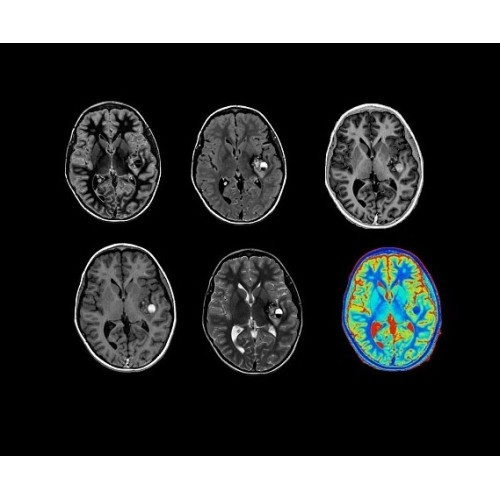

• OncoWorks — клинические приложения для обработки и визуализации анатомических и морфологических данных, специфичных для каждого типа онкологических образований.

• ImageWorks — повысит производительность МРТ благодаря визуализации высокого качества с MAGIC, четкими результатами пост-процессинга с READYView.

Технология полной оцифровки изображения Total Digital Imaging (TDI) предлагает потрясающие достижения в области визуализации:

• Технология Direct Digital Interface (DDI)использует независимый аналого-цифровой преобразователь для оцифровки сигнала от каждого из 128 радиочастотных каналов, что обеспечивает значительное увеличение качества за счет уменьшения фонового шума.

• Технология Digital Micro Switching (DMS)— это следующее поколение технологий радиочастотных катушек, основанное на замене аналоговых схем блокировки сверхбыстрыми микропереключателями (MEMS).

• Digital Surround Technology (DST)— это новая технология объемной оцифровки данных, которая объединяет сигналы от каждого элемента катушки. Прекрасное соотношение сигнал/шум и чувствительность поверхностных катушек в сочетании с превосходной однородностью и высокой проникающей способностью встроенной радиочастотной катушки — все это позволяет создавать качественные изображения не только позвоночника, но и всего тела.